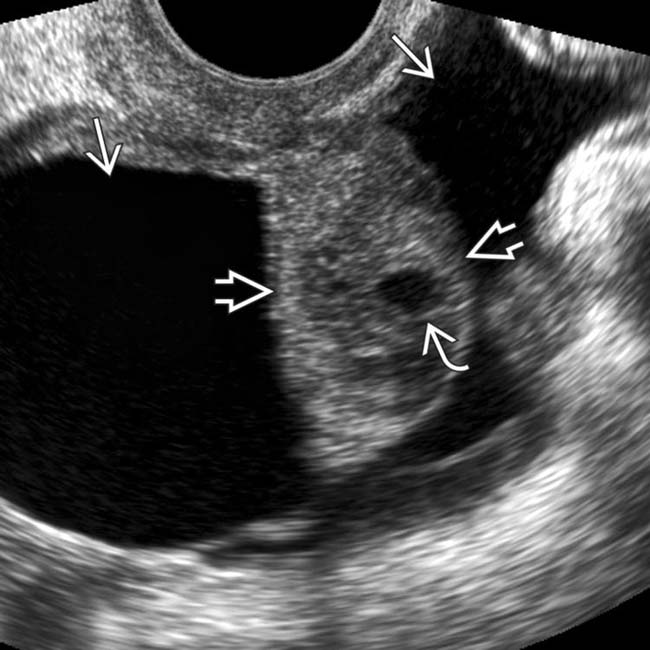

Presentation on Twisted ovarian cyst by Dr. Monnaf

Ovulation happens when these cysts are around 2 to 3 cm in size. Ad learn the early warning signs and symptoms that arise due to ovarian cancer. There are several types of cysts and some can grow very large. Using the formula for a sphere, and assuming water density, a 10 cm. New reply follow new topic.

The female reproductive system, including the ovaries. Benign cysts are routinely produced by the ovaries during the menstrual cycle in women who are premenopausal and frequently by women who are menopausal. Diameter cyst would weigh 523.5 grams or 1.15 pounds. 23 cm is about 9 inches which is a very large cyst. Learn more about the signs that may reveal.